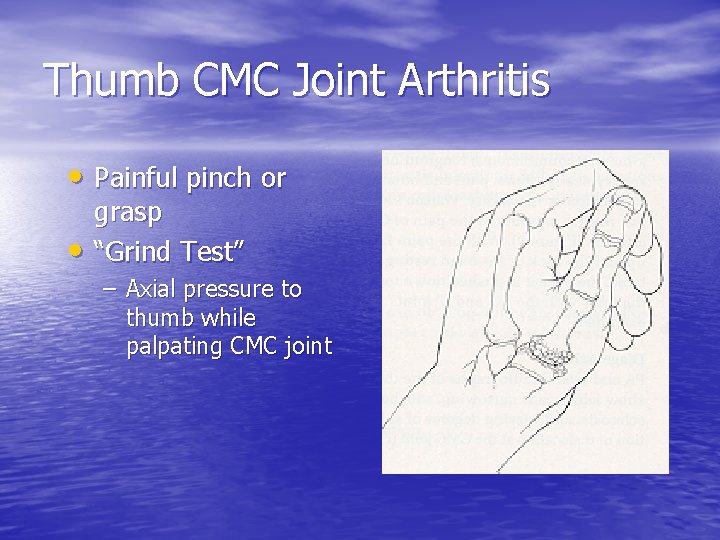

Thumb CMC Joint Arthritis • Painful pinch or • grasp “Grind Test” – Axial pressure to thumb while palpating CMC joint